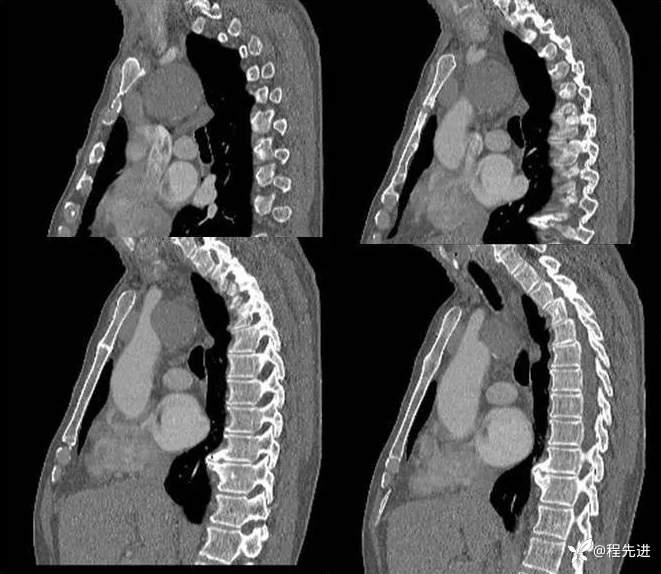

增强静脉期矢状位